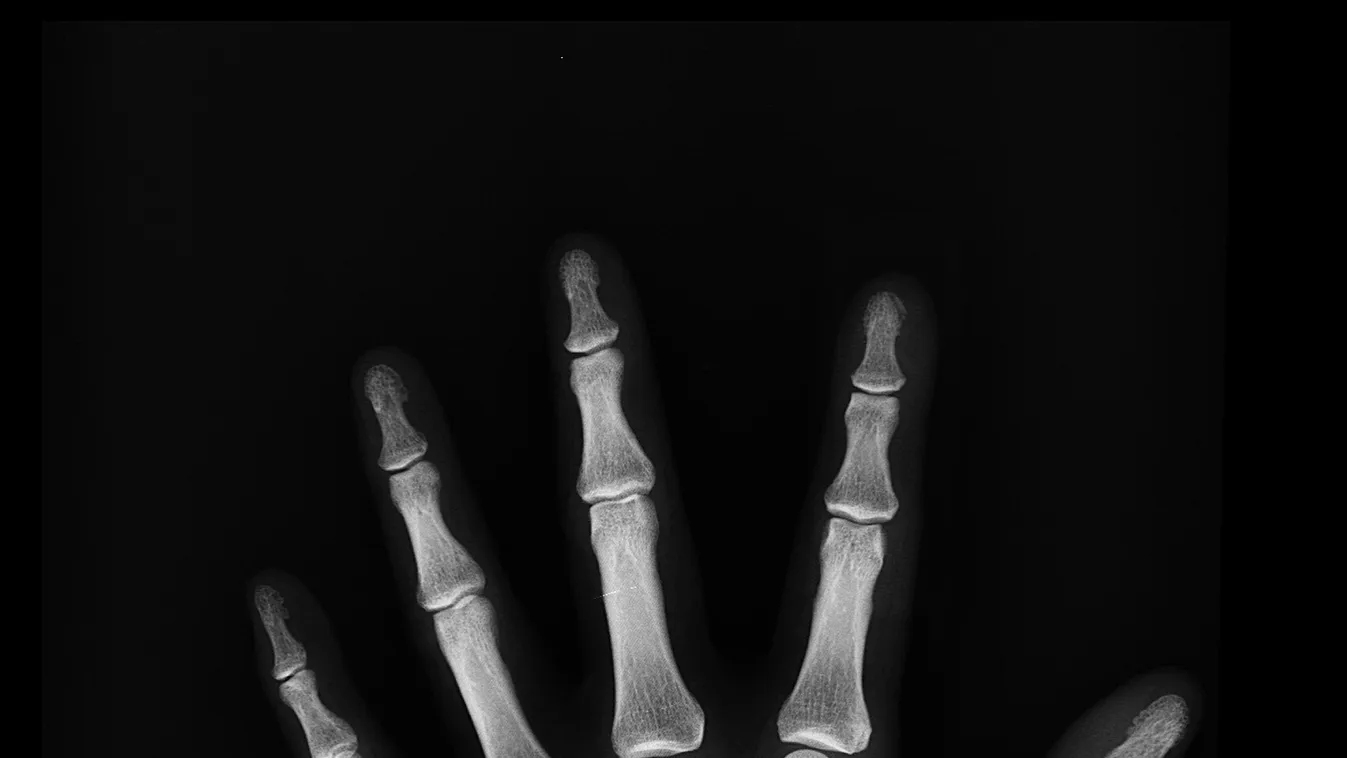

Padlódeszkák darabolása közben, egy elektromos fűrésszel majdnem teljesen kettévágta a bal kézfejét az angol Anthony Lelliott. A 46 éves asztalos egyetlen rossz mozdulattal duplán amputálta magát: levágta a középső ujját, illetve a kézfeje egy darabjával egyben a mutató és a hüvelykujját. A londoni Tootingban működő St. George’s kórház orvosai először sokkot kaptak, amikor meglátták, majd nekiálltak a műtétnek és a csodával határos módon meg tudták menteni a kezét – írja a Sky News.

Lelliott első körben egy tizenhét órás operáción esett át. Az orvosok először helyre tették a törött csontokat, aztán idegeket és érdarabokat műtöttek ki az alkarjából és a lábfejéből, hogy áthidalhassák a csonkolt kézből hiányzó részeket. Az operáció közben az orvosok észrevették, hogy a középső ujjal komolyabb gondok vannak, mint gondolták, ezért úgy döntöttek, azt a testrészt feláldozzák és kéz többi részének megmentésére fókuszáltak. A középső ujj csontjait és bőrét a tenyér rekonstrukciójánál használták fel.

Így sem volt azonban elég bőr a roncsolt kézfejen. Az orvosok kivágtak egy darabot Lelliott bőréből az ágyékánál, majd odavarrták a sérült kézfejet. Két héttel később, amikor az ágyékról elég bőr nőtt át a kézre, a végtagot leválasztották. A plasztikai sebész, Roger Adlard azt nyilatkozta, ez volt a legkomplikáltabb amputációs eset, amivel pályafutása során dolga volt.